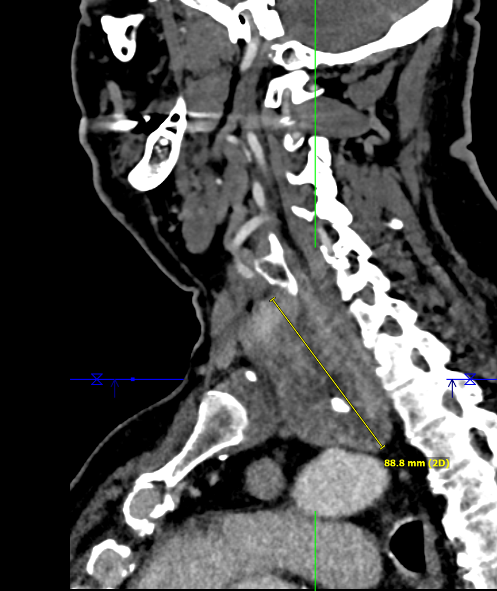

Methodik: Externe Vorstellung des Patienten mit Meläna und vorliegen einer komplexen anatomischen Ausgangssituation bei Zustand nach pyloruserhaltender Pankreaskopfresektion mit Teilresektion der Pfortader aufgrund chronischer Pankreatitis. Zusätzlich besteht eine Pfortaderthrombose mit konsekutivem portalen Hypertonus. In der extern durchgeführten Gastroskopie zeigte sich frisches Blut in den Dünndarmschlingen sowie Ösophagusvarizen Grad III. In der durchgeführten Computertromographie (CT) konnte keine aktive Blutung nachgewiesen werden, jedoch bestanden ausgeprägte portosystemische Kollateralen. Es erfolgte die Übernahme in die Universitätsmedizin Göttingen. Hier erfolgte eine transhepatische Stentimplantation der Vena portae nach erfolgreicher transhepatischer Rekanalisation. Im weiteren Verlauf zeigte sich jedoch in der CT-Untersuchung eine In-Stent-Thrombose, woraufhin eine erneute, jedoch frustrane Rekanalisationsmaßnahme durchgeführt wurde. Entscheidung zur endoskopischen Intervention.